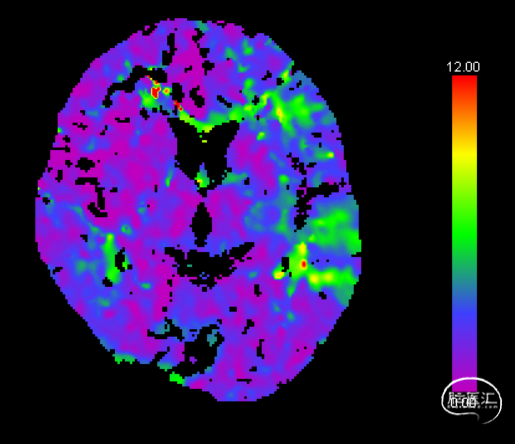

CTP CBF

CTP Tmax

术后1周 颅脑CTA+CTP

Pre-OP CTP Tmax

Post-OP CTP Tmax